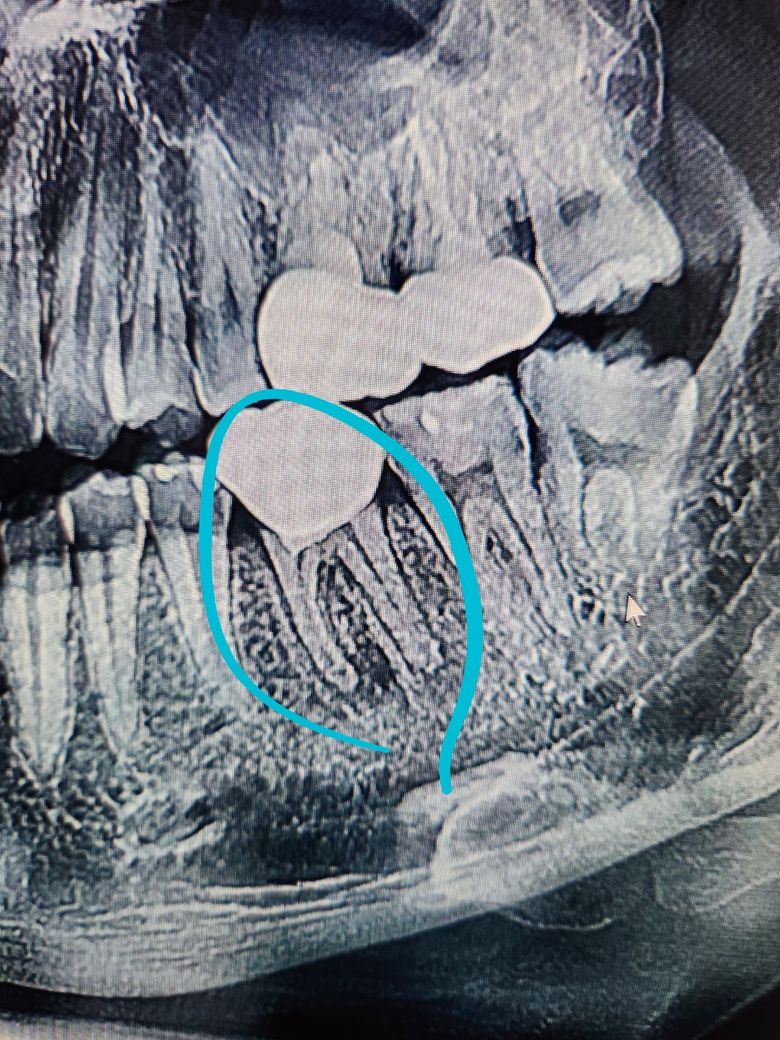

재신경치료해야해서 하늘색 동그라미 뿌리끝 염증인데 석회화로인해서 재신경치료 들어가야 합니다

사진 3장 각각 달마다 다른사진인데 염증이 커지는것같이 보이나요 아니면 다 비슷비슷하나요?

1. 사진 상으로는 염증이 커져보이는지에 대해서는 판단하기 어렵지만 염증의 경계가 불규칙한 것으로 보아 진행성으로 보여집니다. 치료를 하셔야 할 것으로 보입니다.

-염증의 크기는 차이가 없어 보입니다.